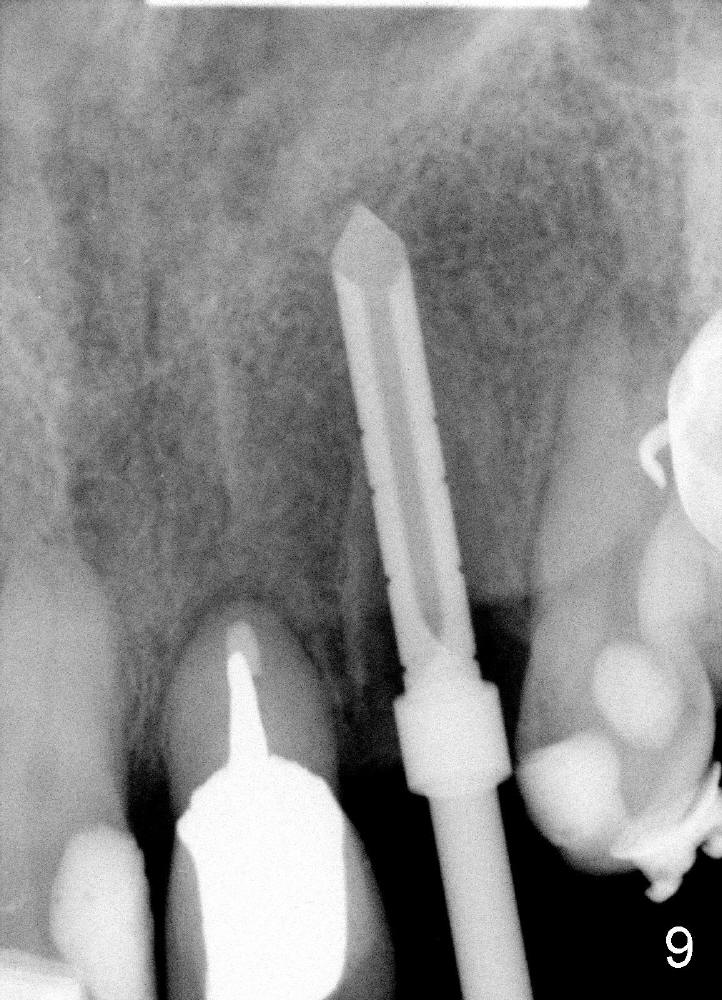

The 2.5 mm reamer is inserted as planned (following the contour of the alveolus (4)). Although the reamer (Fig.7 R) is palatal and there is a gap buccally (*), the handle of the reamer tilts buccally (Fig.8). A straight wall is created by using 2.5 mm reamer (Fig.9). A tapered implant is inserted (3.8x14 mm with apical diameter 2.4 mm, Fig.10). It is supposed to have high torque, but this implant is placed with a knob driver, probably due to osteoporosis. The dilemma is that the patient insists upon immediate provisional. If a tap driver were used, low torque would be found before implantation.